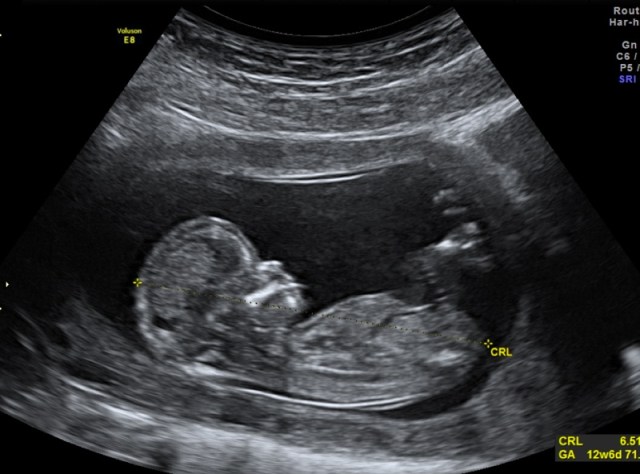

Fetal image helps men take in reality of pending birth, study suggests

Seeing the first ultrasound images of their unborn babies helps fathers bond with their children, according to a new small study.

Researchers interviewed 22 expectant fathers, aged 23 to 41, in Michigan after they viewed a routine ultrasound of their unborn child taken at weeks 16 to 20 of pregnancy. Half of the men were first-time fathers.

The ultrasound helped the men truly understand that they were going to have a child and reassured them that all was well with the pregnancy, the researchers said.